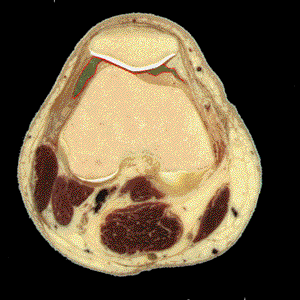

Definición: La bolsa subcuadricipital (bursa suprapatellaris) es la mayor de las 12 bolsas que existen en la rodilla. Se extiende entre el fémur y el cuadriceps y se comunica con la cavidad articular.

Inervación: La bolsa subcuadricipital puede contener un plegamiento sinovial conocido como plica suprapatelar, una variante que representa un remanente de la compartimentalizaci�n e,bri�nica de la articulaci�n de la rodilla.

Función: La bolsa subcuadricipital se comunica con la cavidad articular. Las efusiones de la articulación se vierten en la bolsa subcuadricipital de forma que la presencia de fluídos en dicha bolsa permite el diagnóstico de derrames.